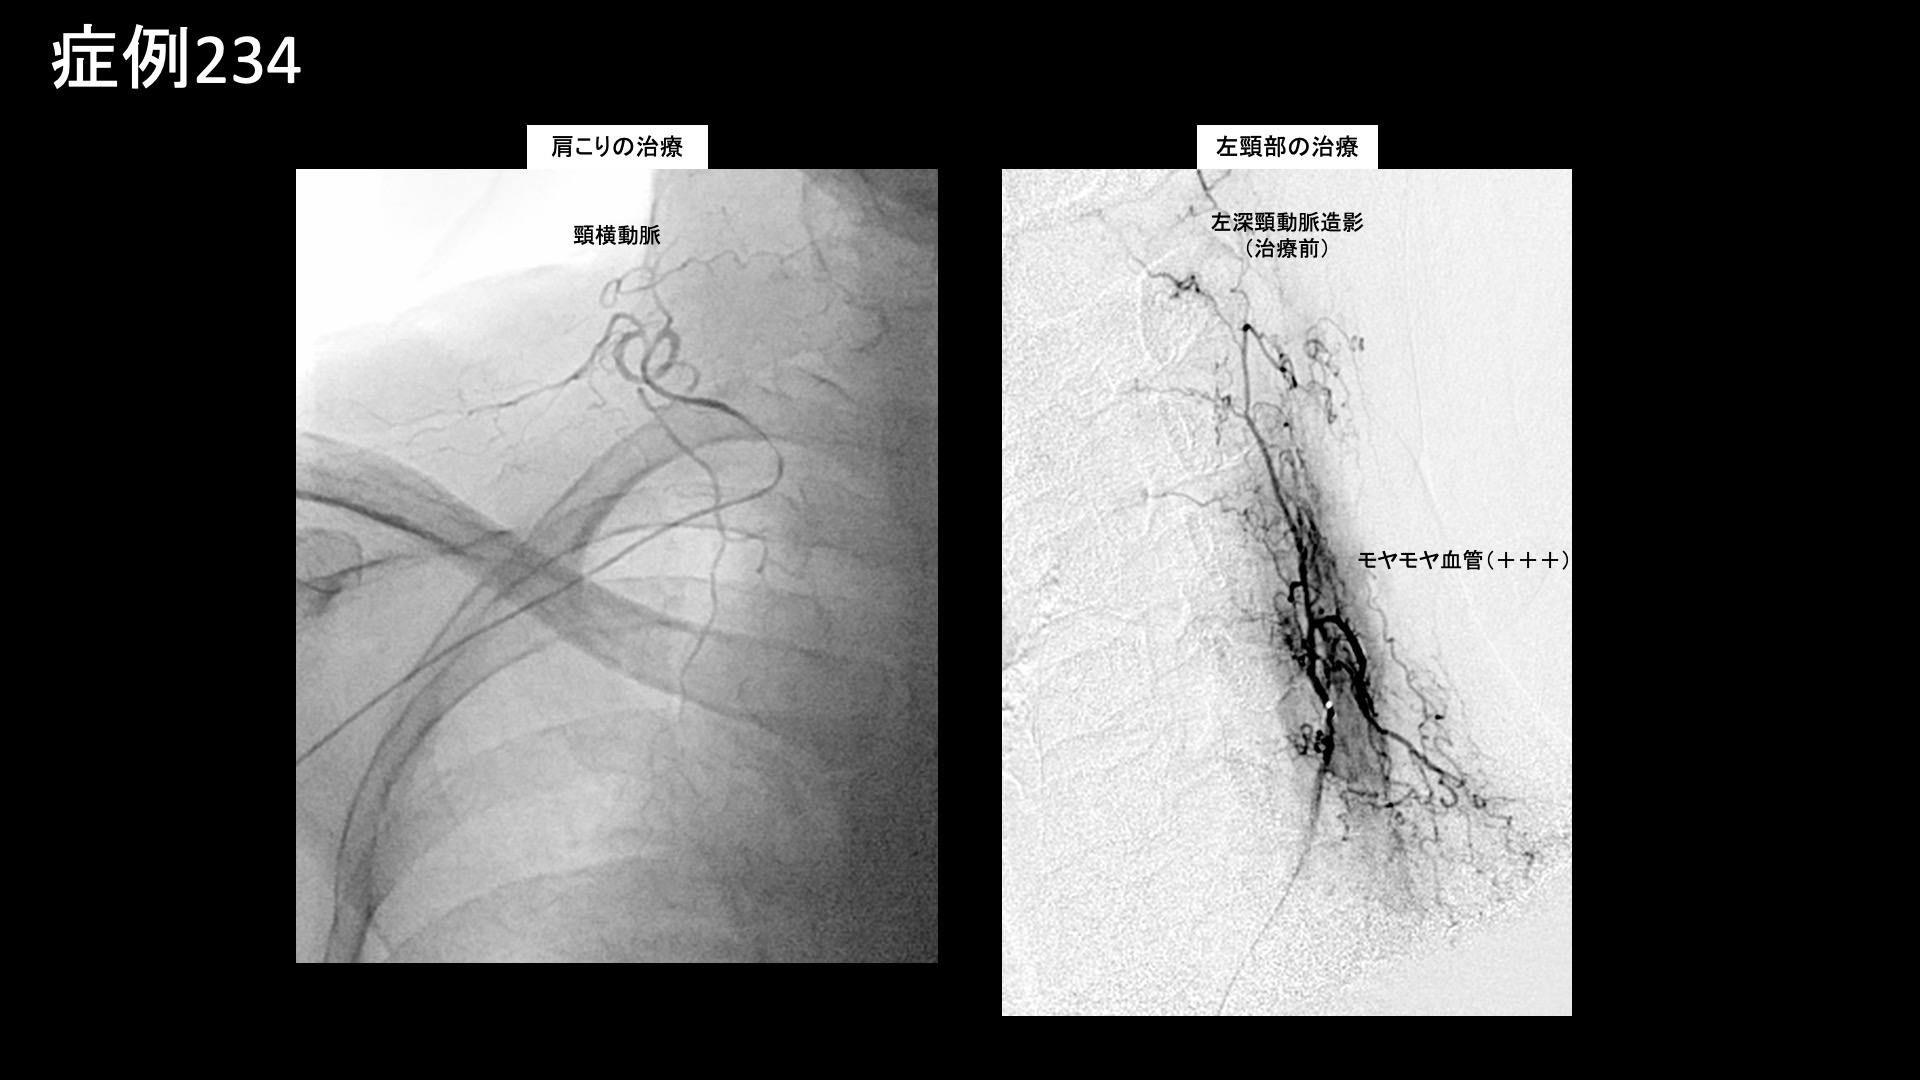

肩:肩こり・四十肩・五十肩 【50代:女性】五十肩も首肩こりも一網打尽、血管から痛みを治すカテーテル治療(五十肩、凍結肩、肩関節周囲炎、首肩こり) 2025.09.05 鴨井院長による動画解説 受診までの経過 重いものをもったことがきっかけで3ヶ月前から右肩が痛むようになりました。病院では五十肩と診断されました。ズキズキと常に痛みがあり、夜も寝られないほどでした。仰向けで寝ることはできませんでした。長年、頭痛や首肩こり(特に左側)がありましたが、それも悪化しているように感じました。 診察時の所見 右肩関節の可動域は、外転90度(真横から腕を挙げる動作で水平までが限界)、外旋45度、反対の肩に手を回すことはできず、後ろに手を回しても臀部に触れることしかできないなど、大きく制限されていました。レントゲンでは異常ありませんでしたが、エコー検査では肩関節前方からの観察において炎症に伴うモヤモヤ血管を反映した異常血流信号を認めました。腱板などの組織損傷はありませんでした。治療適応と判断し、モヤモヤ血管(病的新生血管)に対する運動器カテーテル治療(微細動脈塞栓術)を受けていただきました。 治療の所見 肩関節において血管造影を行うと、肩甲上動脈や烏口枝にてモヤモヤ血管が濃染像として描出されました。首肩こりの治療では、症状の強さに合致して、特に左深頸動脈で同様にモヤモヤ血管が描出されました。それぞれ、治療後は画像上速やかに消失しました。その他複数箇所の治療を行い終了しました。 治療後の経過 治療後2週間くらいで夜間痛がとれてきました。寝られるようにもなり、治療後1ヶ月くらいになると7割方の症状は改善し(3/10程度)、肩こりも感じなくなりました。頭痛はまだ多少ありました。痛みがとれてきたので、後は可動域だけだなと思えるようになりました。治療後2ヶ月、9割方の症状が改善し(1/10程度)、腕も上がるようになりました。外転145度まで回復していました。この間、特別なリハビリを行ったわけではありません(ほとんどの場合で不要です)。ご遠方であり、その後の受診は途絶えていますが、ここまでくればぶり返す心配はなく、残りの症状もじきに完全に消失します。五十肩はカテーテル治療によりまず間違いなく改善すると言える疾患です。頭痛や首肩こりを合併している場合は、一緒に治療可能ですので、併せてご相談いただければと思います。 五十肩の詳しい病状説明はこちら 【60代:男性】切らずに治すヘルニア治療!1ヶ月前から増悪した10年来の腰痛に対するモヤモヤ血管治療(腰椎椎間板ヘルニア、筋・筋膜性疼痛症候群) 前の記事 【60代:男性】マラソンランナーを悩ませた繰り返す肉離れによるふくらはぎの痛み(腓腹筋痛症)に対するモヤモヤ血管治療 (腓腹筋痛症、肉離れ後遺症) 次の記事